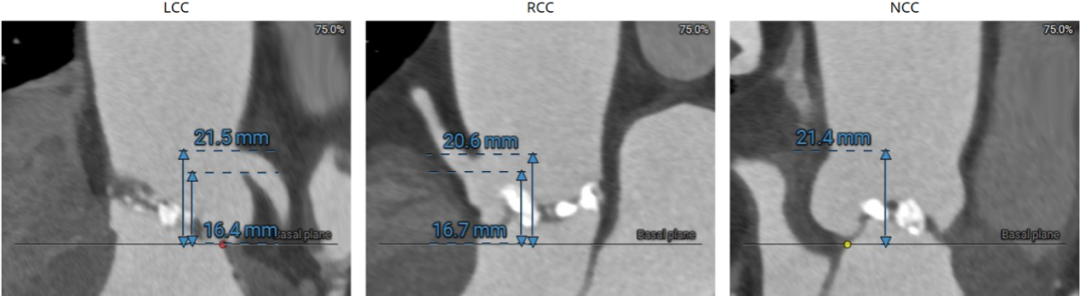

主动脉瓣根部:

左冠近端钙化: